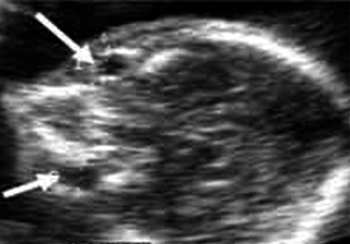

Δισχιδής ράχη

Γενικά: Ανοιχτή ΣΣ με συνοδό έλλειμμα υπερκείμενου δέρματος

Συχνότητα: 1/2.500 γεννήσεις περίπου.(6,23)

ECHO - ευρήματα στο 2ο τρίμηνο:

- Η ΣΣ εμφανίζει σε εγκάρσιες τομές εικόνα (U), με κηλικό σάκο να προβάλει από το οστικό έλλειμμα και ποικίλο περιεχόμενο.

- Παραμόρφωση μετωπιαίων οστών, συνεπάγεται κρανίο σε σχήμα λεμονιού.(38)

- Παρεγκεφαλίδα σε σχήμα μπανάνας λόγω εξαφάνισης της παρεγκεφαλονωτιαίας δεξαμενής.(36)

- Διεύρυνση των πλαγίων κοιλιών (70%).(28)

- Οι κινήσεις των άκρων μπορεί να είναι φυσιολογικές, ακόμα και σε μεγάλα ελλείμματα του σπονδυλικού σωλήνα.

- Το κρανίο σε σχήμα λεμονιού βρίσκεται σε ποσοστό 45% πριν τις 24εβδ., σε 50% μεταξύ 24-35εβδ. και 0% μετά την 35εβδ. Εάν η βλάβη εντοπίζεται στην ιερά μοίρα, το σημείο ανευρίσκεται στο 100%.(19,38)

- Η παρεγκεφαλίδα σε σχήμα μπανάνας ανευρίσκεται σε ποσοστό 99% πριν την 24 εβδ. Αργότερα παρατηρείται απουσία ή σμίκρυνση του μεγέθους της.(19)